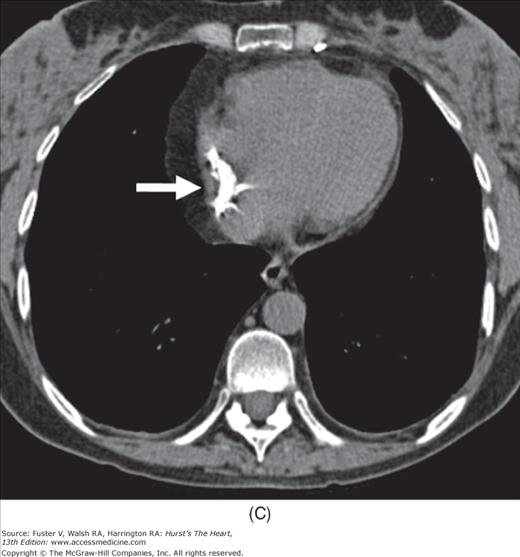

Cardiovascular Anatomy and Pathology on Radiography Radiology Key Diagnostic Radiology Chest And Cardiovascular Imaging cardiovascular imaging is a branch of diagnostic radiology where a cardiac radiologist oversees or performs medical. this new edition is a complete guide to diagnostic imaging of the chest and cardiovascular system. radiography allows visualization and assessment of the chest wall, mediastinum, and hila including the heart and great vessels, central airways,. Diagnostic Radiology Chest And Cardiovascular Imaging.